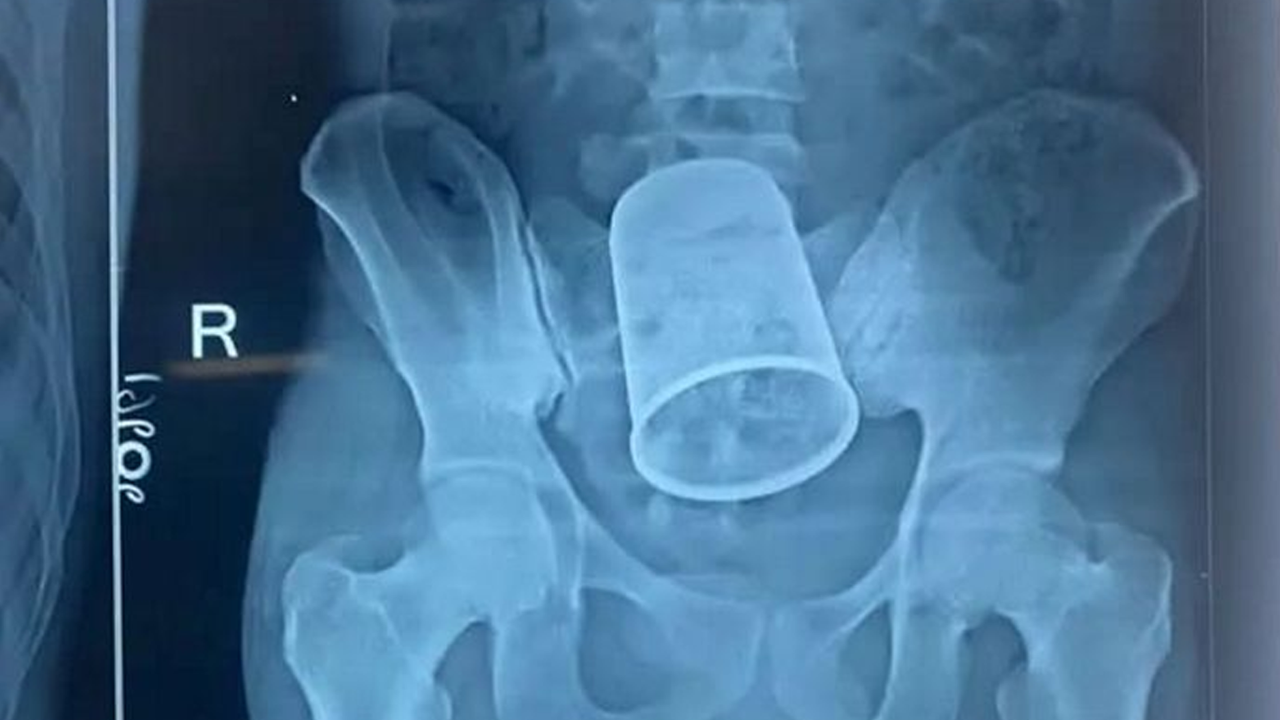

A 22 year old bloke from India was rushed to hospital after getting a 15-cm-long steel cup stuck in his anus after a night on the piss.

The cup, which was 7cm in diameter, was blocking Kumar's bowel movements, causing him agonising stomach pains.

When doctors ran body scans, they found the steel cup in the man's body, and proceeded to perform surgery for two and a half hours to get it removed.